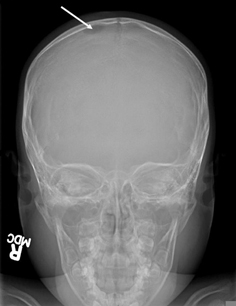

The classical appearance on x-ray is a punched-out lytic lesion, most commonly in the skull, with sharply demarcated margins, and little or no periosteal reaction.[55]Azouz EM, Saigal G, Rodriguez MM, et al. Langerhans' cell histiocytosis: pathology, imaging and treatment of skeletal involvement. Pediatr Radiol. 2005 Feb;35(2):103-15.

Commonly, there is an associated mass that can extend intracranially and may cause brain compression. By contrast, lesions involving the orbit, mastoid, or other areas of the skull base are often extensive and irregular, with a soft-tissue component that must be differentiated from a malignant tumor.[55]Azouz EM, Saigal G, Rodriguez MM, et al. Langerhans' cell histiocytosis: pathology, imaging and treatment of skeletal involvement. Pediatr Radiol. 2005 Feb;35(2):103-15.

[Figure caption and citation for the preceding image starts]: Skull x-ray showing lytic bone lesion in the right posterior parietal area of the skullFrom the personal collection of Oussama Abla, MD; used with permission [Citation ends].